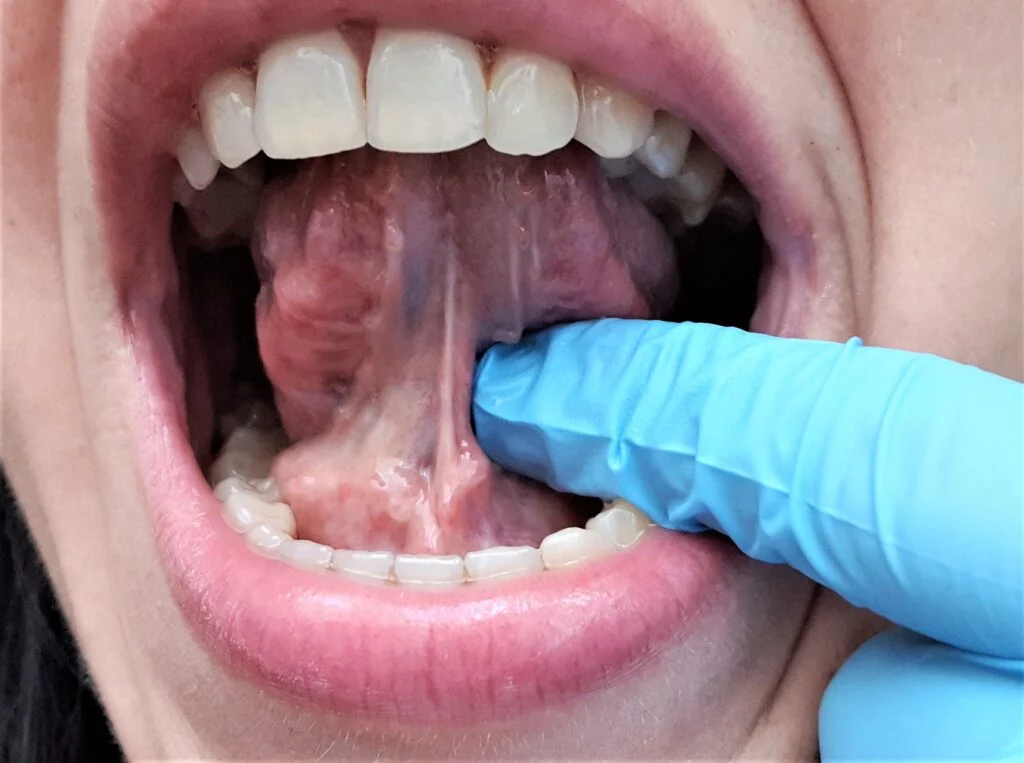

Wędzidełko (frenulum) to cienka fałda błony śluzowej łącząca ruchomą część jamy ustnej z nieruchomym podłożem. W obrębie jamy ustnej wyróżniamy trzy klinicznie istotne wędzidełka: wędzidełko języka (frenulum linguae), wędzidełko wargi górnej (frenulum labii superioris) oraz wędzidełko wargi dolnej (frenulum labii inferioris). Każde z nich może — przy nieprawidłowej budowie lub lokalizacji przyczepu — powodować specyficzne problemy kliniczne.

Najczęstszym wskazaniem do zabiegu w Łodzi jest ankyloglosja (przywiązanie języka) — zbyt krótkie lub zbyt grube wędzidełko języka ograniczające unoszenie czubka języka do podniebienia. Skutkuje to trudnościami przy karmieniu piersią u noworodków, w artykułowaniu głosek językowych u dzieci i problemami z higieną jamy ustnej u dorosłych. Druga najczęstsza sytuacja to wędzidełko wargi górnej z niskim przyczepem, które ciągnie brodawkę dziąsłową między siekaczami i uniemożliwia samoczynne zamknięcie diastemy po leczeniu ortodontycznym.

Ankyloglosja (tongue-tie) to wrodzona anomalia, w której wędzidełko języka jest zbyt krótkie, zbyt grube lub zbyt nisko przyczepione — co ogranicza unoszenie języka do podniebienia i jego wysuwanie poza linię zębów. Stopień ograniczenia oceniamy skalą Kotlow I–IV lub narzędziem BTAT (Breastfeeding Assessment Tool).

4. Frenotomia lub frenektomia – nacięcie lub wycięcie

W frenotomii lekarz wykonuje jedno lub dwa poprzeczne nacięcia wędzidełka — zwalnia napięcie i rozszerza zakres ruchomości. W pełnej frenektomii wycina się całe wędzidełko razem z wiązką tkanki łącznej biegnącą do brodawki dziąsłowej. Przy dyskomforcie lub zwiększonej podatności na krwawienie stosujemy laser diodowy: cięcie bezporównania precyzyjniejsze — bez krwawienia, bez szwów, krótszy czas gojenia.